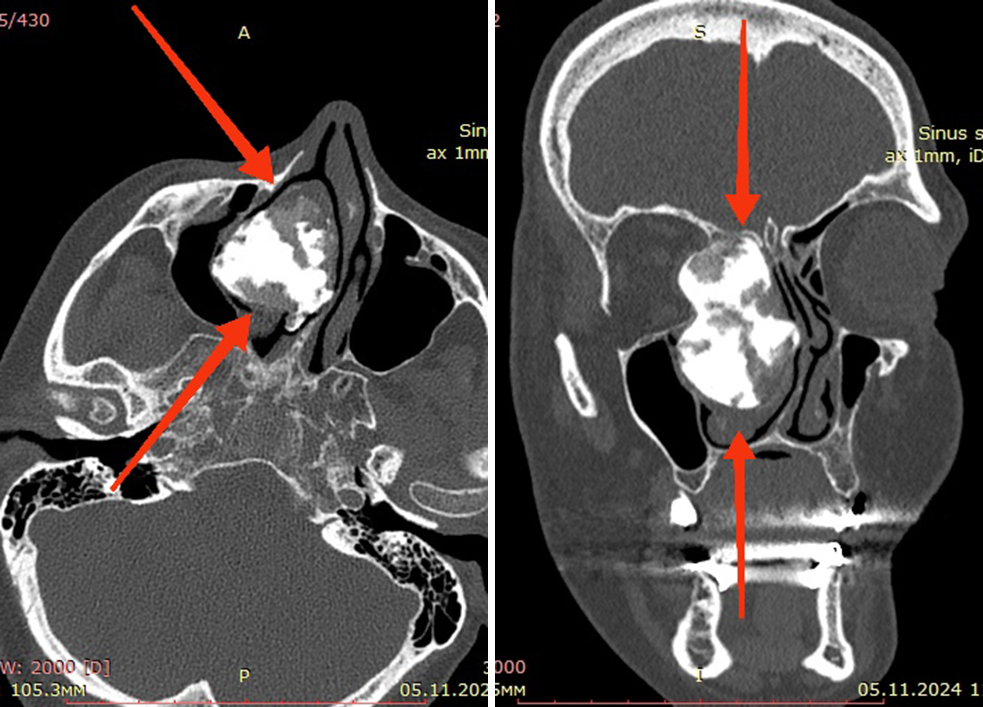

За медпомощью женщина обратилась только после того, как у нее появились лицевые боли и стало исчезать обоняние. Томография позволила неврологу по месту жительства предположить развитие необычайно большой, но доброкачественной опухоли костной ткани – остеомы. Она росла в правой половине носа, раздвигая его стенки и распространяясь в орбиту глаза и лобную пазуху. В результате существенно сместилась не только носовая перегородка, но и стенка верхнечелюстной пазухи.